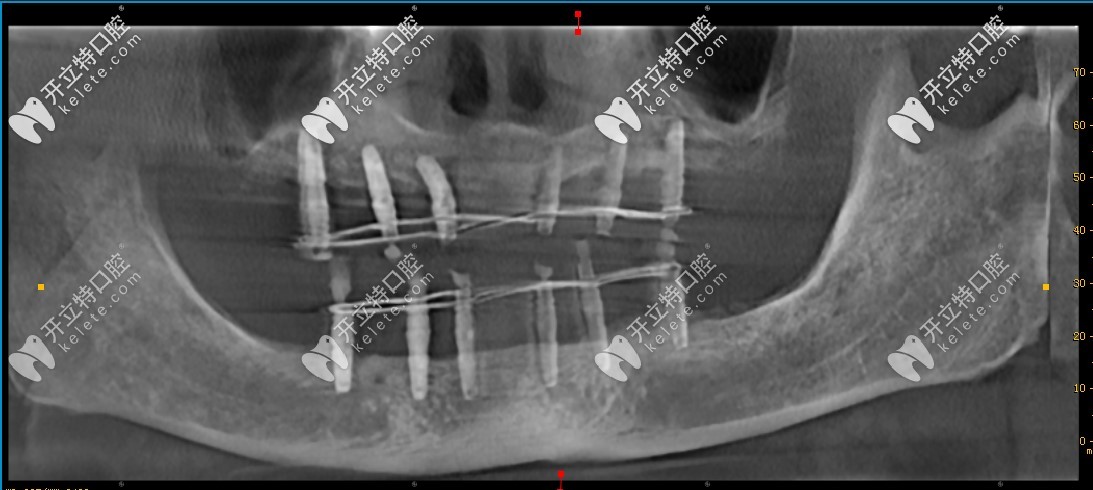

治療過(guò)程:在手術(shù)中,洛九龍口腔的劉院長(zhǎng)采用UN德國(guó)咬合重建系統(tǒng),細(xì)心為顧客種植12顆植體,手術(shù)時(shí)間共計(jì)兩個(gè)半小時(shí),手術(shù)非常成功,接下來(lái)僅需等待植體愈合,佩戴牙冠即可。

來(lái)看效果:從牙片來(lái)看,植體已經(jīng)植入牙槽骨內(nèi),接下來(lái)只需等待三個(gè)月的恢復(fù)期即可,不管是植入的深度或角度,都非常好!